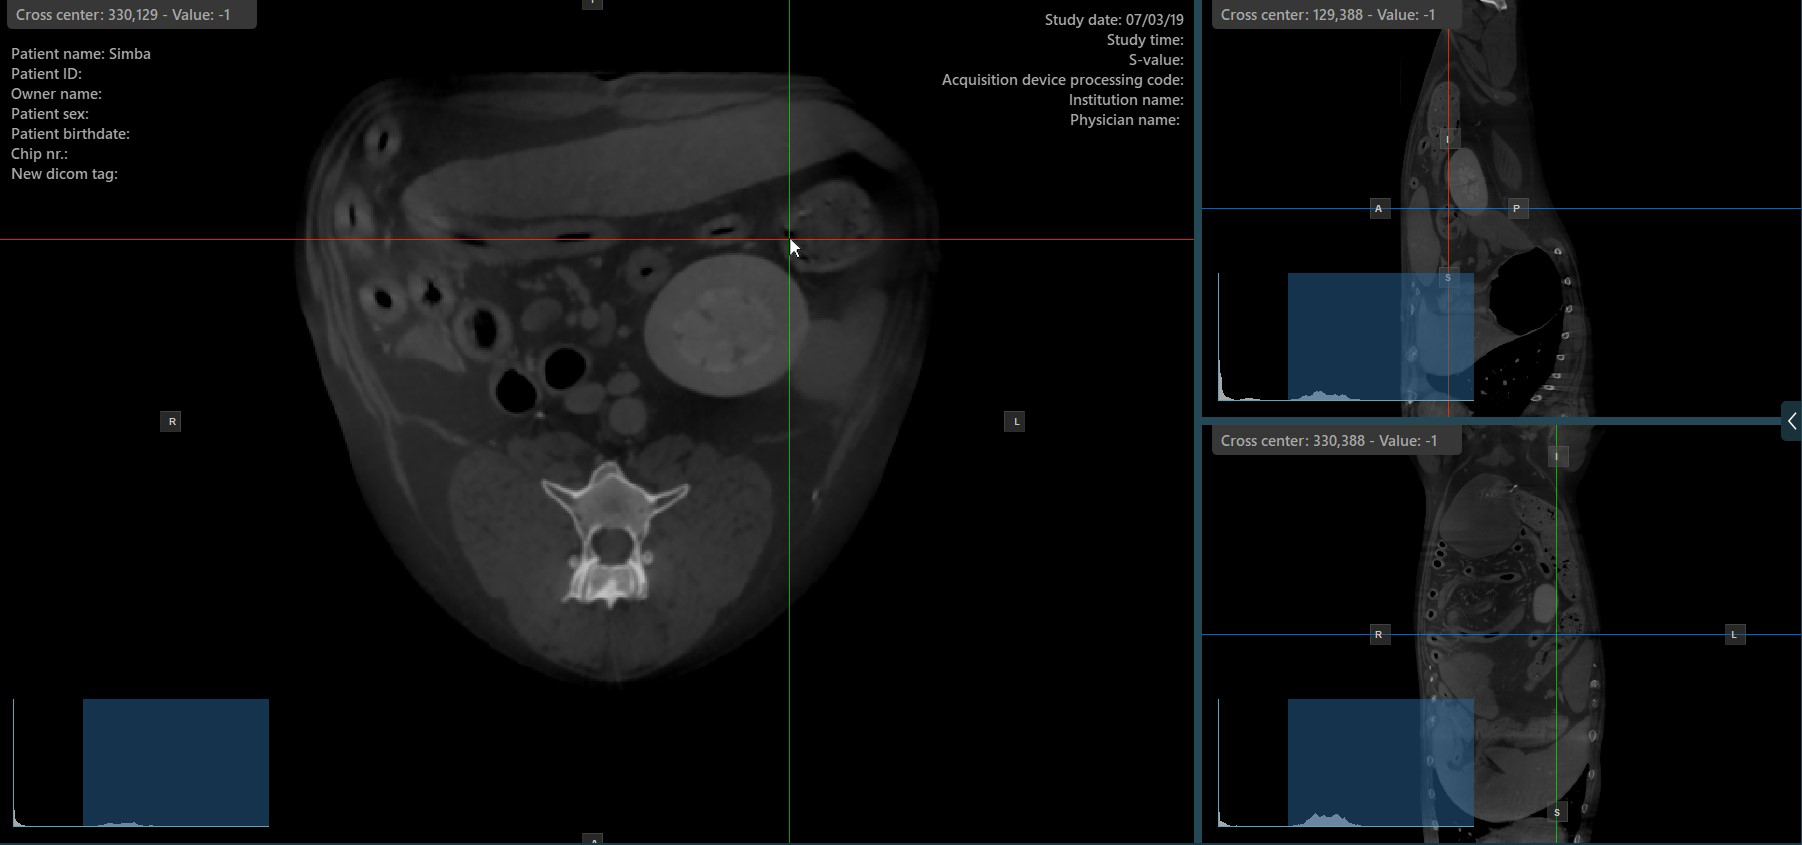

Slicer-Kreuzmittelpunkt ändern¶

Das Ändern der Position des Kreuzmittelpunkts der Slicer verändert die Position der entsprechenden zwei Bildebenen. Der Kreuzmittelpunkt der Slicer kann mit dem Werkzeug Select Item (Default) ausgewählt werden, das standardmäßig der rechten Maustaste zugewiesen ist.

Sobald der Kreuzmittelpunkt der spezifischen Slicer ausgewählt ist, ziehen Sie ihn in die gewünschte Richtung, um seine Position zu verschieben. Die Orientierung der entsprechenden Bildebenen ändert sich entsprechend.